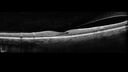

Paracentral acute middle maculopathy - isolated92 views83 year old man New spot in the vision yesterday left eye.

Medical Hx: Pure Hypercholesterolemia

Systemic Meds: Crestor.

VA OD: Dcc20/20

VA OS: Dcc20/20

IOP: TP: OD:19 OS:10